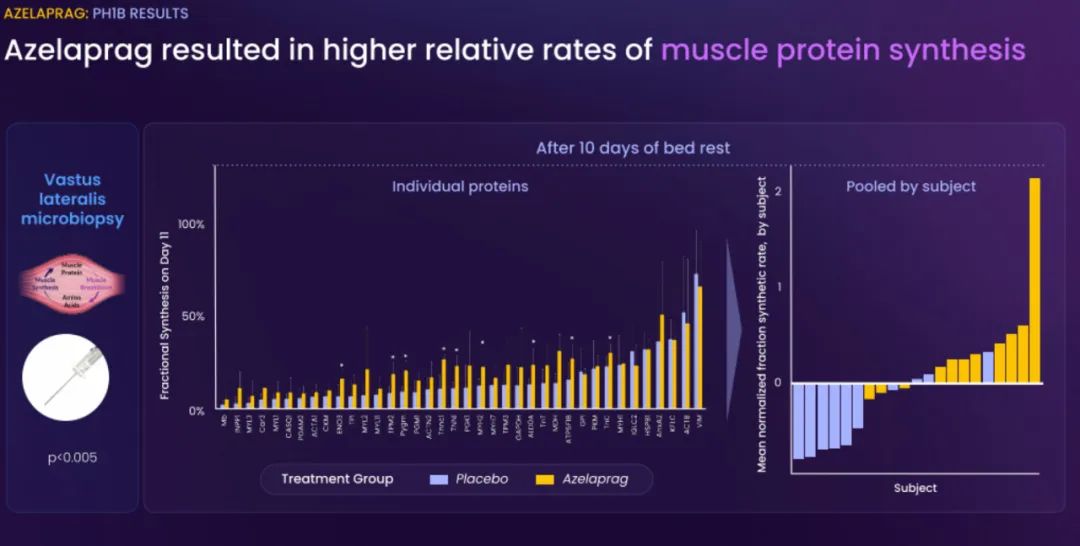

BioAge Labs的主要关注点是代谢疾病,这是全球最大的医疗保健挑战之一。BioAge Labs的主要候选产品 Azelaprag是一种口服小分子,在8个 1 期临床试验中,265 名受试者的耐受性良好。在临床前肥胖模型中,azelaprag 显示出能够使胰高血糖素样肽-1 受体 (GLP-1R) 激动剂诱导的体重减轻增加一倍以上,同时恢复健康的身体成分并改善肌肉功能。

这些临床前结果得到BioAge Labs在卧床老年人中进行的 1b 期临床试验的支持,在该试验中,BioAge Labs观察到在 10 天内接受 azelaprag 治疗的受试者的肌肉萎缩减少、肌肉质量保持良好并且新陈代谢得到改善。